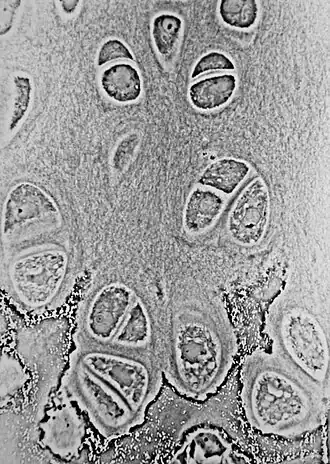

Los condrocitos (del griego chondros, ‘cartílago’ + kytos, ‘célula’) son un tipo de célula que se encuentran en el cartílago. Se encargan de mantener la matriz cartilaginosa, a través de la producción de sus principales compuestos: colágeno y proteoglicanos.[1][2] Los condrocitos conforman solo el 5% del tejido cartilaginoso, pero son esenciales para el mantenimiento de la matriz extracelular, la cual comprende el 95% de este tejido.[1]

Imagen tomada con un microscopio óptico en la que se observan condrocitos formando parte del cartílago hialino.